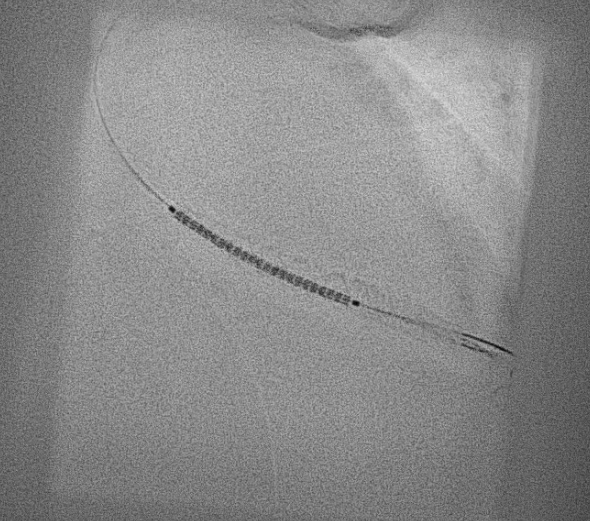

Intracoronary GTN was given after predilatation. IVUS showed mostly fibrous plaque with plaque extending from the distal RCA to the proximal RPDA. Reference diameters (EEL) were 4.5mm proximally in the distal RCA and 2.75mm distally in the RPDA. PCI to the distal RCA to RPDA with a provisional approach, using a stent with high postdilatation limits across the bifurcation.

PCI was performed with a 7Fr JR4 Guide with wires in the RPDA and RPL. Lesion was predilated and stented with a 2.75x33m DES and postdilated with a 4.5mm NC proximal to the RCA bifurcation. IVUS showed underexpansion distally and severe malapposition proximally hence the stent was further postdilated with 2.75mm NC distally and 4.5mm in the distal RCA. ClearStent showed unravelling of the stent, which was confirmed on IVUS with a new total stent length of 52mm. The distal RCA diameter had grown in size to 5mm at the site of the proximal stent edge. A 4.5x24mm DES was implanted in the distal RCA to cover the unravelled stent struts, which was postdilated with a 5mm NC balloon. Final IVUS showed the stent to have adequate apposition with no immediate complications.